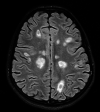

Viral infections can serve as a trigger for variable autoimmune, antibody-mediated demyelinating disorders. There is accumulating evidence that the severe acute respiratory syndrome coronavirus 2 (SARS-CoV-2) virus, causing coronavirus disease 2019 (COVID-19) infection and responsible for the current worldwide pandemic, can lead to a cascade of immune-mediated brain and spinal cord demyelinating injuries. However, such observation in the pediatric age group was only reported in very few patients. Thus, the heterogeneous spectrum of this phenomenon in children is still unfolding. We are reporting a case series of five pediatric patients with a variety of acute central nervous system (CNS) demyelinating disorders in the context of acute or recent COVID-19 infection. A 16-year-old female with anti-myelin oligodendrocyte glycoprotein (MOG) disorder, an eight-year-old male with acute disseminated encephalomyelitis (ADEM), a 13-year-old female with neuromyelitis optica spectrum disorder (NMOSD), and two 14 and 13-year-old females with new-onset multiple sclerosis (MS) are reported, all of whom presented acutely following COVID-19 infection. We propose that para and post-infectious CNS demyelinating disorders can potentially follow acute COVID-19 infection in children. Considering SARS-CoV-2 testing as a part of diagnostic workup is possibly useful. Awareness of the presence of this phenomenon can help in the recognition and management of those patients.